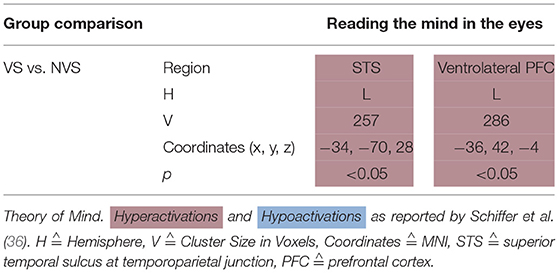

Affective Theory of Mind

Schiffer et al. (36) showed a picture of a person's eyes to their participants and let them select—out of two words—the one that fitted best the person's emotional state. They found that, when performing this task, VS as compared to NVS hypoactivated the left ventrolateral PFC and left superior temporal sulcus at the temporoparietal junction (see Table 6).

Schiffer et al. (36) found that, when performing an affective ToM task, VS as compared to NVS hypoactivated the left ventrolateral PFC and left superior temporal sulcus at the temporoparietal junction.

Synthesis of Findings From Studies Using Affective Theory of Mind Paradigms

In Figure 5, we provide an overview on activation patterns generated by affective theory of mind paradigms. The only study reporting on this area was performed by Schiffer et al. (36). Hyperactivations were present in the left inferior frontal gyrus and the left superior temporal sulcus reported in the group comparison of violent as opposed to non-violent persons with schizophrenia. Here, activation of the inferior frontal gyrus is compatible with a challenge in language comprehension, while the superior temporal sulcus is known to be implicated in social perception and general theory of mind.

Figure 5. Affective theory of mind activations. Overview of the affective theory of mind brain activation patterns reported by the reviewed studies, the group comparison being VS vs. NVS in the contrast of mental state attribution vs. gender discrimination. Here, we show the hyperactivation of VS>NVS in red (shown slice numbers are 170, 180, 190, 200).